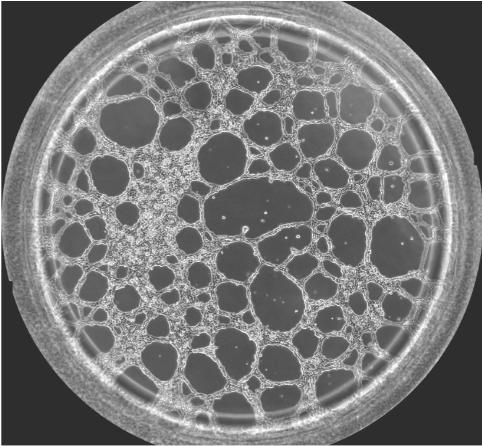

圖一 血管生成鏡檢圖

無論原發(fā)性腫瘤還是繼發(fā)性腫瘤,一旦生長直徑超過1~2 mm,都會有血管生成。這是由于腫瘤細胞自身可分泌多種生長因子,誘導血管生成。多數(shù)惡性腫瘤的血管生成密集且生長迅速。因此,血管生成在腫瘤的發(fā)展轉(zhuǎn)移過程中起到重要作用,抑制這一過程將能明顯阻止腫瘤組織的發(fā)展和擴散轉(zhuǎn)移。于是體外的血管生成實驗就能很好的模擬腫瘤的血管發(fā)生過程,并且適合研究藥物對這一過程的影響實驗。本實驗以HUVEC細胞為例,介紹這一實驗的詳細過程。

可以按照細胞的生長速度定時采集圖像,并且對其成管長度,覆蓋面積,成環(huán)數(shù),結點數(shù)進行測量和記錄,并且對其進行統(tǒng)計分析。